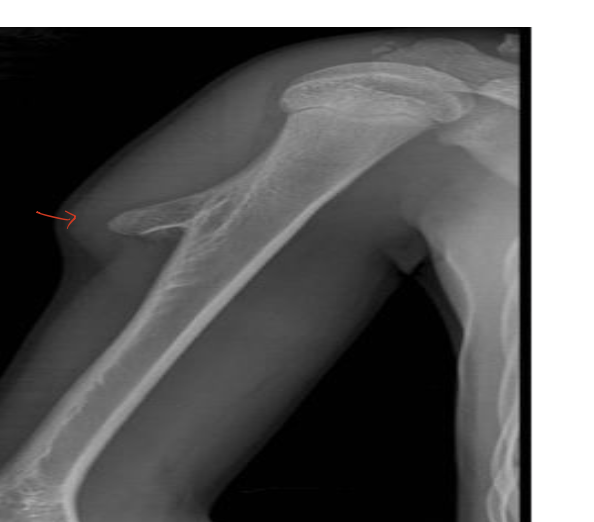

type of fracture ?

SAY everything